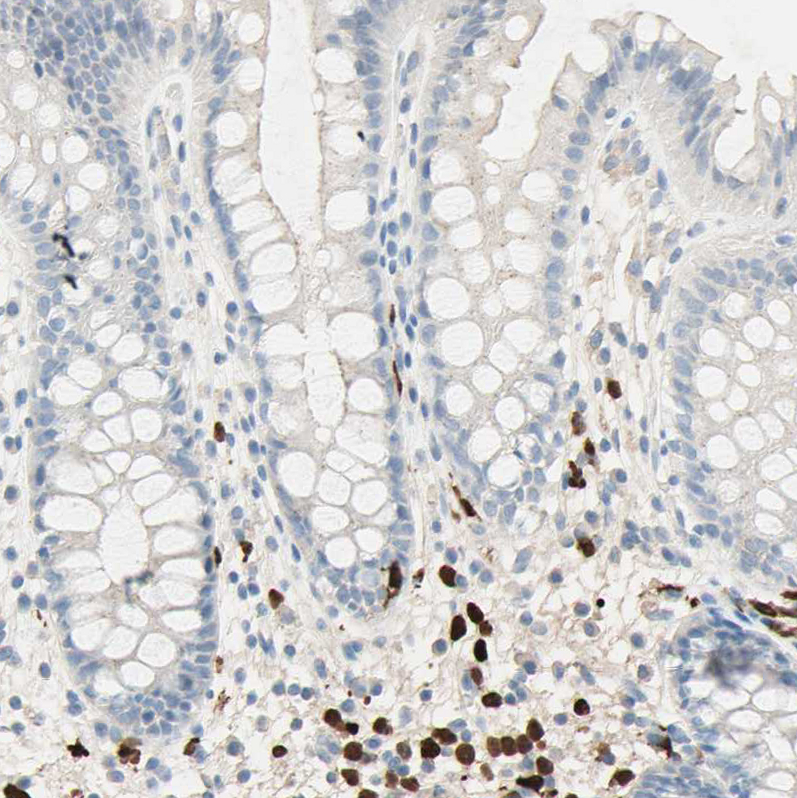

Immunohistochemistry analysis in human bone marrow and cerebral cortex tissues using HPA010547 antibody. Corresponding NFKBIZ RNA-seq data are presented for the same tissues.